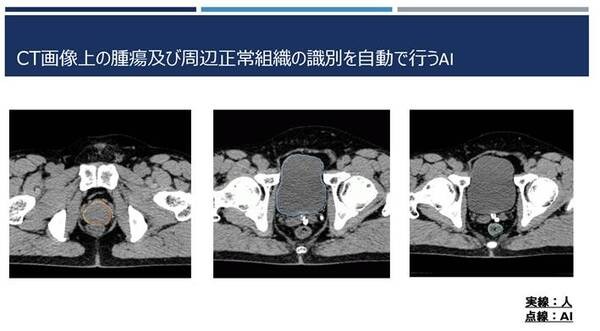

このブレイクスルーとしてひょうご粒子線メディカルサポートが取り組んでいるのが、治療日に撮影したCT画像上の腫瘍と周辺正常臓器の輪郭を作成するAIシステムの開発。通常は医師がCT画像上でこの作業を行うが、輪郭の作成には概ね3~5時間を要する。また、この作業は医療知識だけでなく、ソフトウェアのスキルや経験も求められる。ひょうご粒子線メディカルサポートはこの作業をAIの活用により効率化・高速化することを目指している。

すでに単純CTのみで高い精度の輪郭を作成することに成功しているモデルも多く、例えば医師が前立腺をCT画像上で抽出する場合、30分程度を要すが、ひょうご粒子線メディカルサポートが開発したAIは、たった1分で90%という高い精度で認識することができる。また、複数の臓器を高速に同時抽出することも実現している。